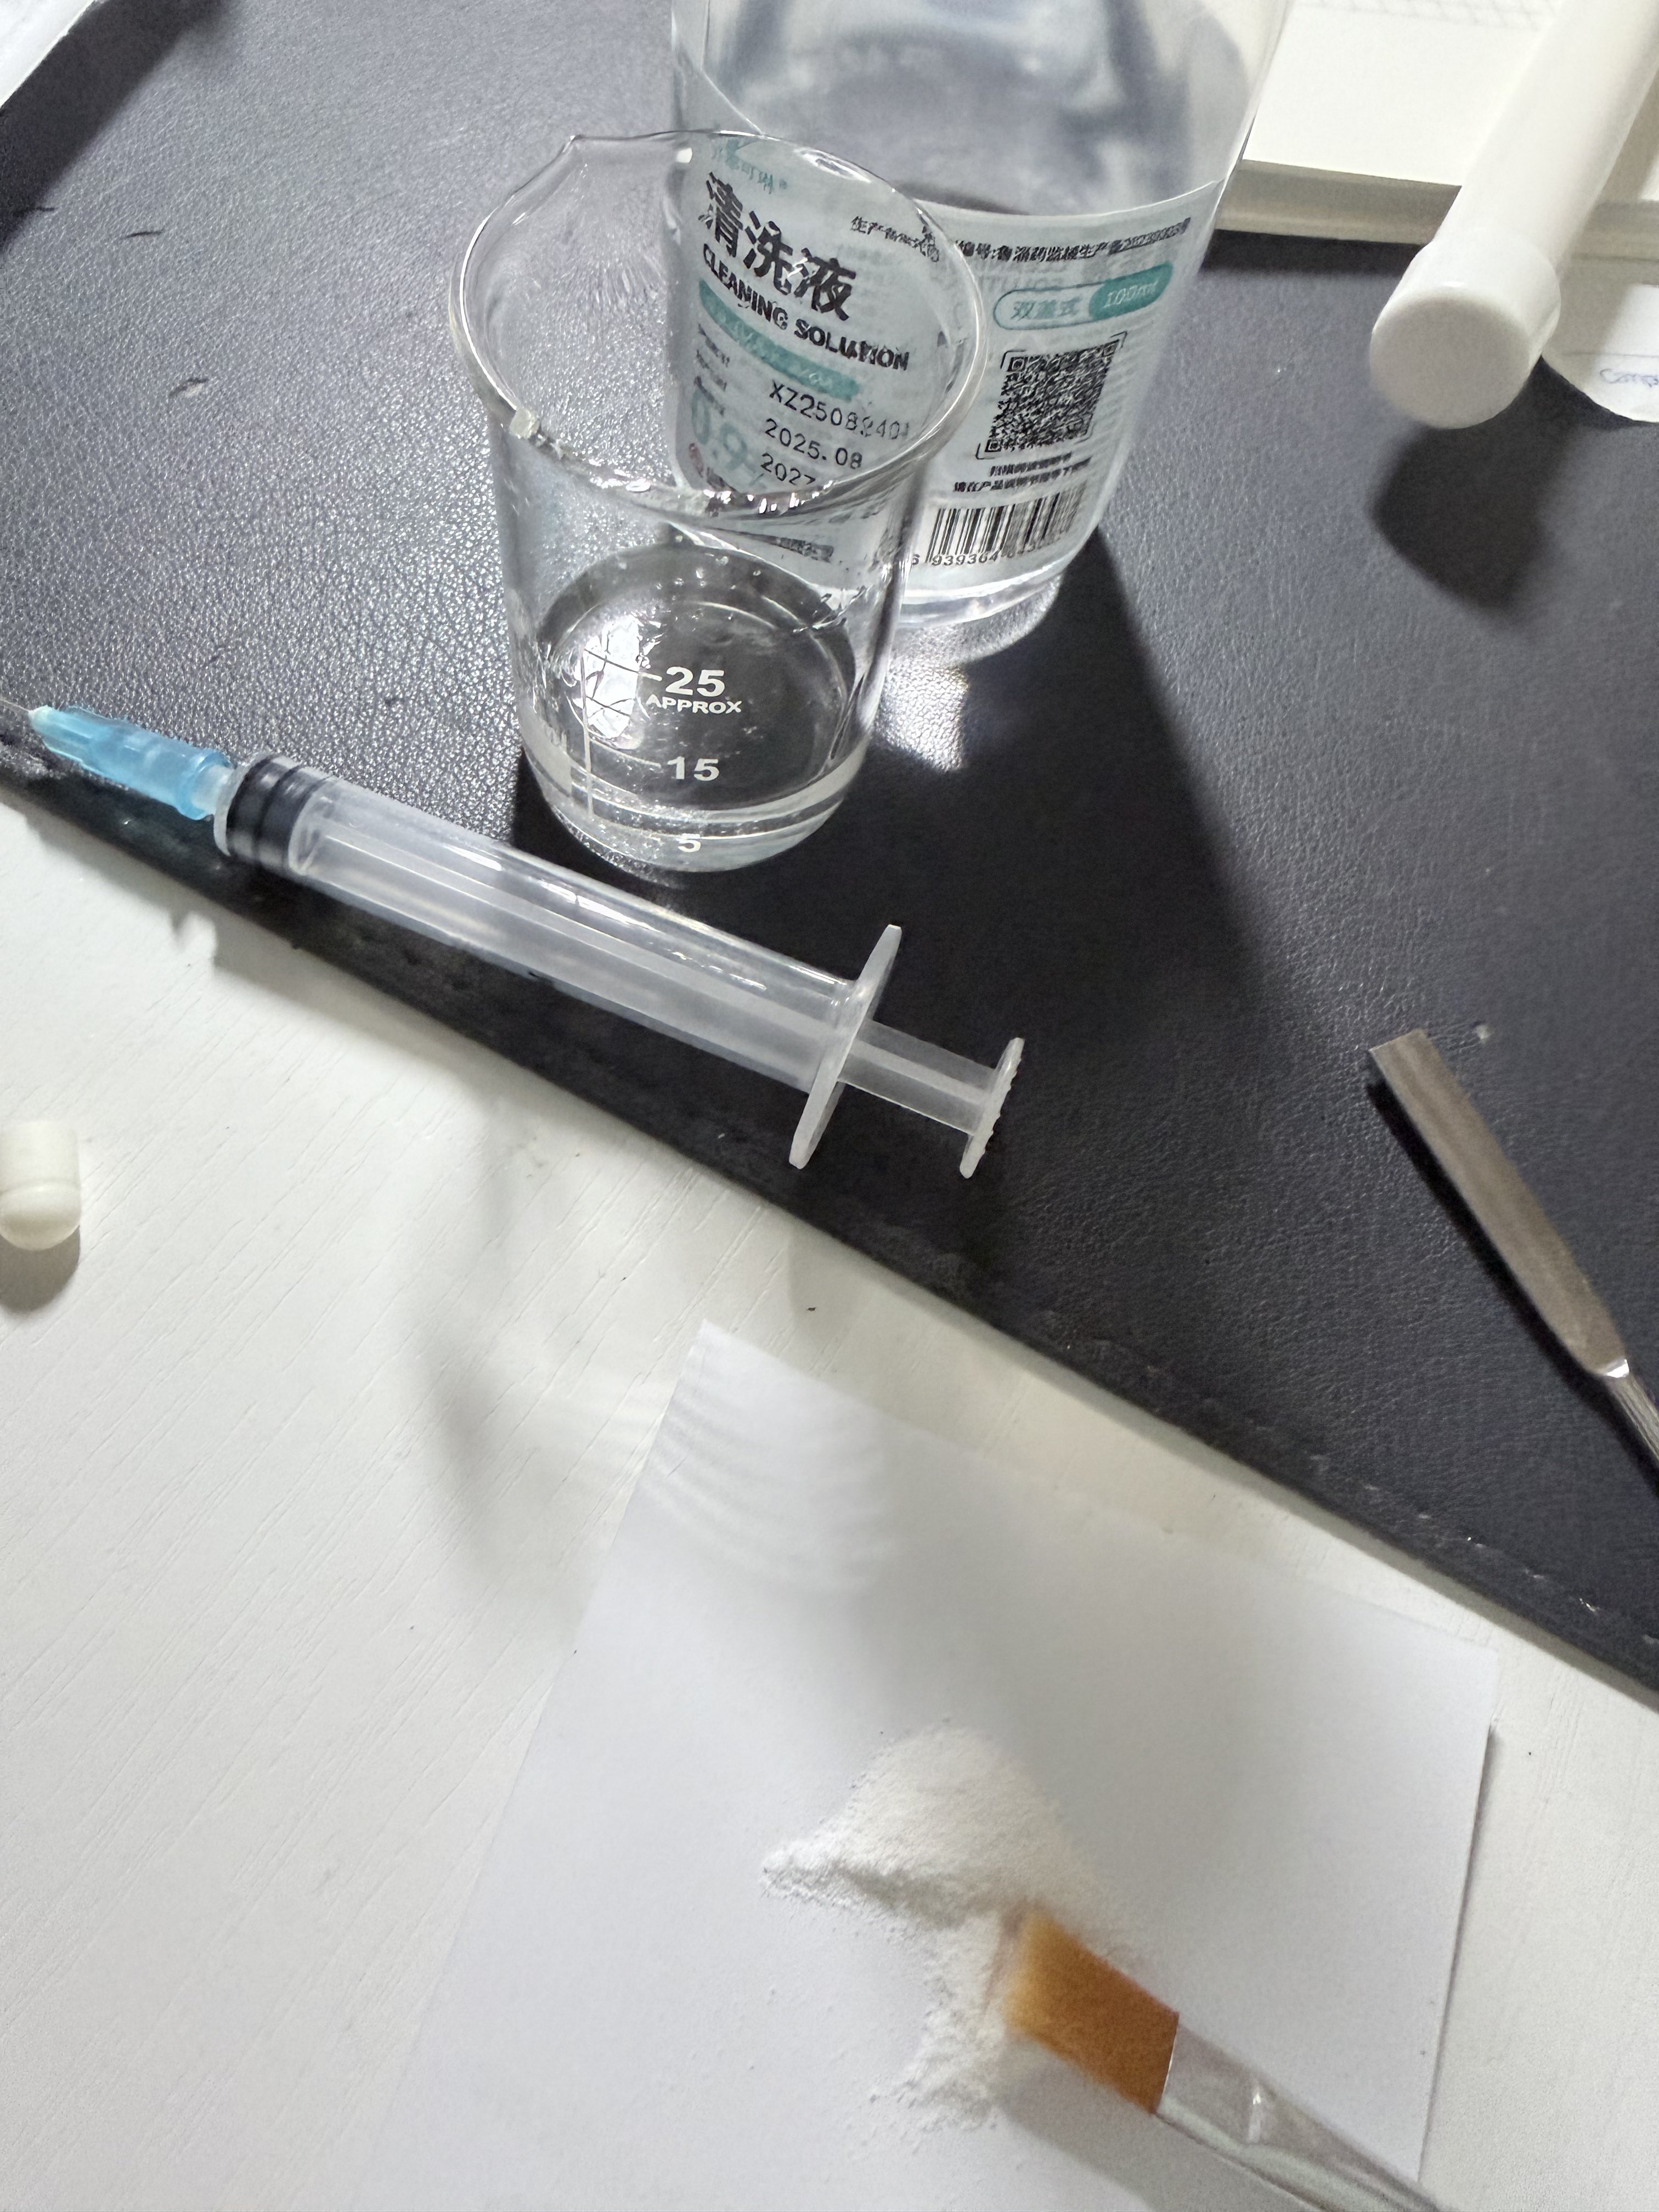

对于药物过量引起的中枢神经系统副作用,有一些不常见或常见的药物来控制症状。

炽烈已极 @AnIncandescence纳洛酮:可用于阿片类药物过量(可获取的上市药品)需舌下给药,因肝脏首过代谢口服时利用度很低;效果持续30-90min;亦可用于酒精中毒的促醒等,但谨慎使用。